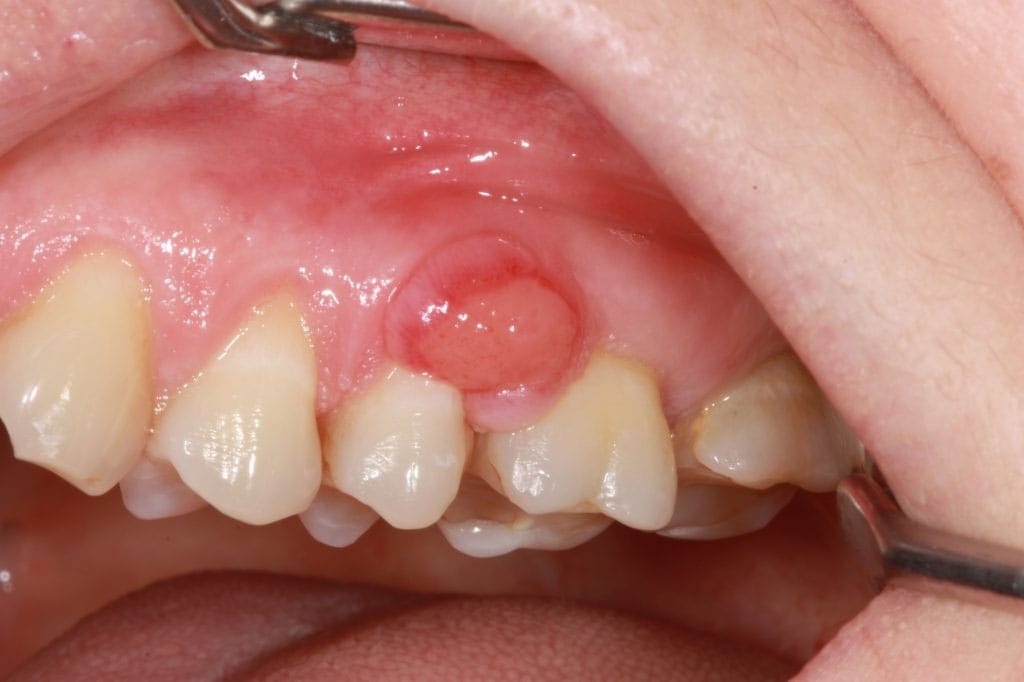

Orofacial granulomatos (OFG) – läpp/ansiktssvullnad

Orofacial granulomatos (OFG) är en granulomatös sjukdom som ofta ger läppsvullnad, gingivala hyperplasier och perioralt erytem. Orsaken är okänd men kan kopplas till överkänslighet mot kanel, bensoater och Crohns sjukdom. Behandling inkluderar kostrestriktion, kortisonsköljning och infektionsterapi

Orofacial granulomatos (OFG) är ett granulomatöst sjukdomstillstånd som framför allt drabbar barn och ungdomar, men kan även ses hos vuxna. Med granulom avses ett infiltrat av inflammationsceller där man bland annat kan se makrofager som smält samman till jätteceller. Granulombildningen i sig är ett ospecifikt tillstånd som kan ses vid flera olika tillstånd såsom sarkoidos, orofacial granulomatos, infektioner och vid främmandekropp-reaktioner.

KLINISK BILD